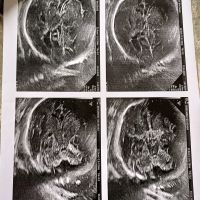

Siêu âm thai có nang não thất tuần 34, 36 và tuần 38

Em chào bác sĩ. Thai em hiện tại hơn 38 tuần. Em đo độ mờ da gáy là 1 mm đi khám tất cả đều ổn e bé phát triển các chỉ số đều bình thường nhưng đến tuần 34 đi khám tại phòng khám bác sĩ lại bảo e bé có nang não...